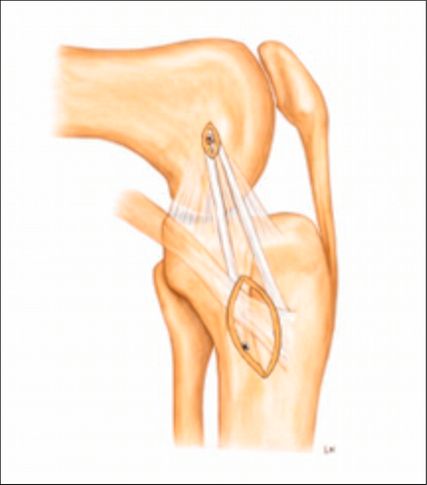

Arthroskopische Instabilitätszeichen: „floating meniscus“ und „drive-through sign“

In einer Level-I-Studie an Patient:innen mit kombinierten VKB- und Grad-II-MCL-Verletzungen (nach Fetto und Marshall) und „Floating-Meniskus-Zeichen“ zeigte die Patientengruppe nach MCL-Augmentation mittels gestielter autologer Gracilis-Sehne signifikant weniger VKB-Revisionen, eine geringere residuale MCL-Laxität sowie bessere patient:innenberichtete Outcome-Scores nach 24 Monaten im Vergleich zu Patient:innen mit isolierter VKB-Rekonstruktion und konservativ behandeltem MCL. Die Abbildung 1 zeigt das „Floating-Meniskus-Zeichen“, ein arthroskopisches Zeichen der medialen Instabilität, bei dem sich der mediale Meniskus vom tibialen Plateau abhebt, infolge einer meniskotibialen Läsion des tiefen Innenbandes. Aufgrund einer zusätzlichen Läsion des oberflächlichen Längsbandes kommt es zu einer medialen Gelenköffnung, die als „medial drive-through sign“ bezeichnet wird.

Anteromediale Tenodese

Die anteromediale Tenodese unter Verwendung der gestielten Gracilis- oder Semitendinosus-Sehne dient der Augmentation bzw. Rekonstruktion sowohl des tiefen als auch des oberflächlichen medialen Kollateralbandes (d/sMCL) über zwei funktionelle Bündel. Abhängig vom zugrunde liegenden Verletzungsmuster kann der Eingriff über einen minimalinvasiven oder einen offenen Zugang durchgeführt werden. Die Technik eignet sich bei akuten Eingriffen in Kombination mit einer MCL-Naht bzw. Refixation im Sinne eines „Bio-Brace“. Darüber hinaus kann sie bei chronischen Fällen mit leichter bis moderater anteromedialer Instabilität mit oder ohne VKB-Rekonstruktion durchgeführt werden. Der Ablauf eines solchen Eingriffes ist wie folgt: Die Sehne wird proximal mittels offenen Sehnenstrippers entnommen, während die tibiale Insertion erhalten bleibt. Die femorale Fixation der gedoppelten Sehne erfolgt im hinteren Anteil des nativen Ansatzes des oberflächlichen Längsbandes, während das freie Sehnenende im Zentrum der distalen tibialen Insertionsstelle des oberflächlichen medialen Kollateralbandes fixiert wird. Eine detaillierte Beschreibung der Operationstechnik ist über den QR-Code (Abb. 2,3) als Videoanleitung abrufbar.1